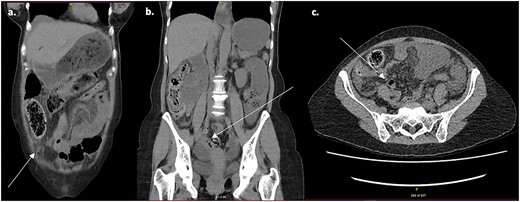

A non-contrast computed tomography scan (CT) of the abdomen and pelvis (contrast shortage) demonstrated a small bowel obstruction with bowel wall thickening in the ileum and associated free fluid, and transition point within the left lower quadrant. Retrospectively it appears the CT demonstrates the adhesion of both the sigmoid colon and transverse colon to a structure in the right iliac fossa (Fig. 1).

Non-contrast CT scan of the abdomen and pelvis. (a) Axial slice demonstrating transverse colon adhered to structure in right iliac fossa. (b, c) Coronal and axial slices demonstrating sigmoid colon adhered to structure in right iliac fossa.